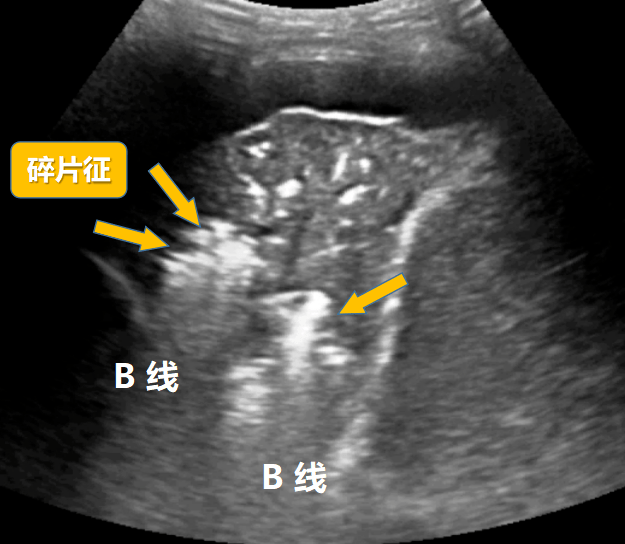

肺超声在肺实变中能辨识哪些肺组织结构

图片尺寸625x544